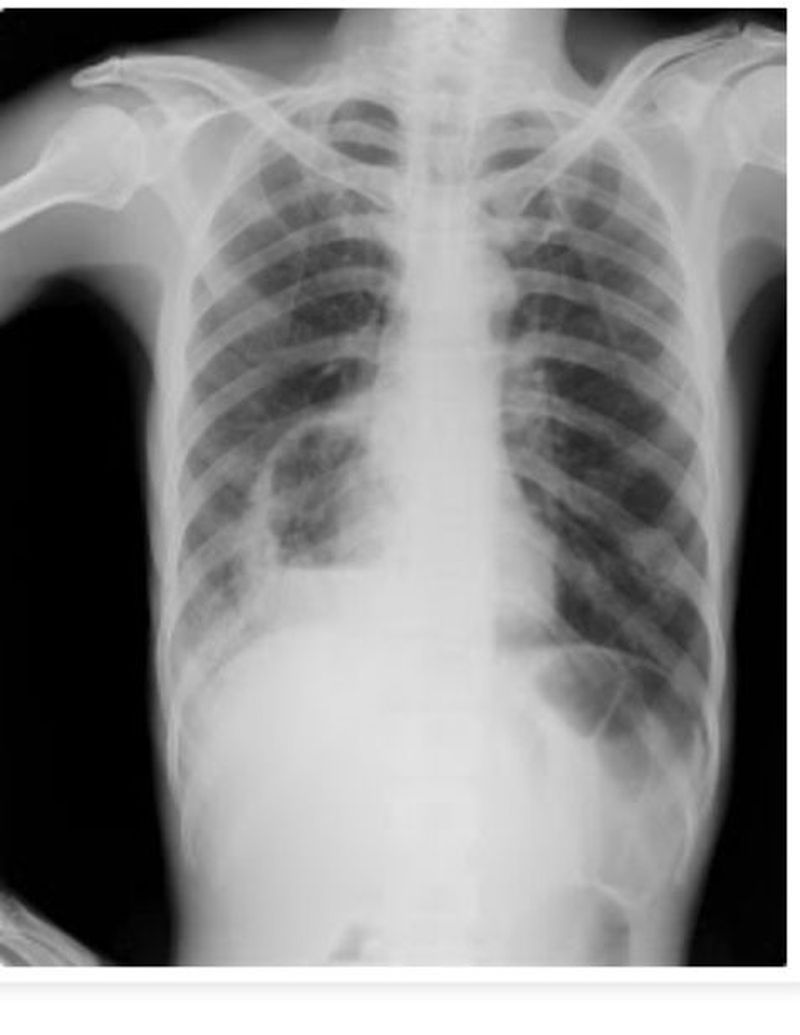

45 year old male with history of high grade fever and foul smelling expectorations .

Findings on the chest radiograph?